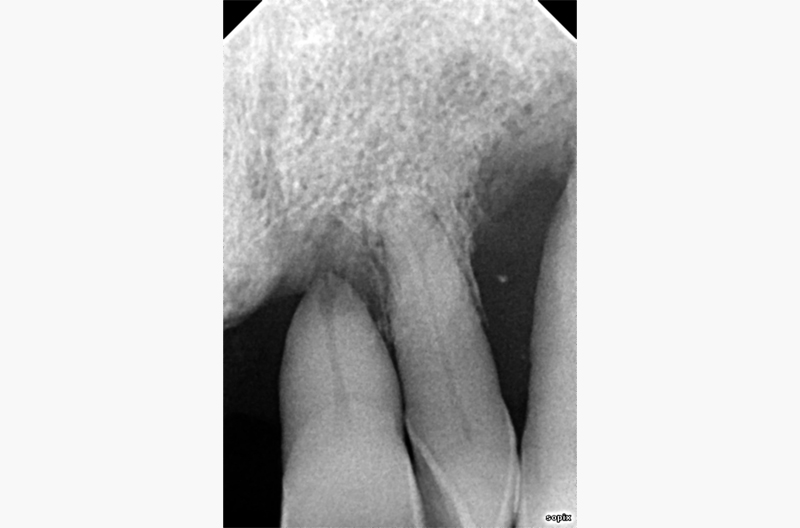

In prima visita viene effettuato un attento esame del cavo orale oltre ad una panoramica delle arcate dentarie, per valutare radiograficamente l’apparato dentale, lo stato di malattia parodontale e il tessuto osseo residuo

(Fig. 1). La paziente in sede di visita esprime la volontà di voler riabilitare solo la parte superiore, perché è quella che le causa maggiore disagio dal punto di vista estetico e relazionale (Fig. 2); pertanto si decide di

effettuare delle radiografie endorali mirate, per valutare la situazione parodontale degli elementi dentali anteriori superiori (Figg. 3a-c).

FIGG. 3a-c – Rx endorale del settore anteriore superiore rispettivamente 12-11, 21-22 e 22-23. Si noti l’importante perdita ossea a carico di 21 e soprattutto di 23